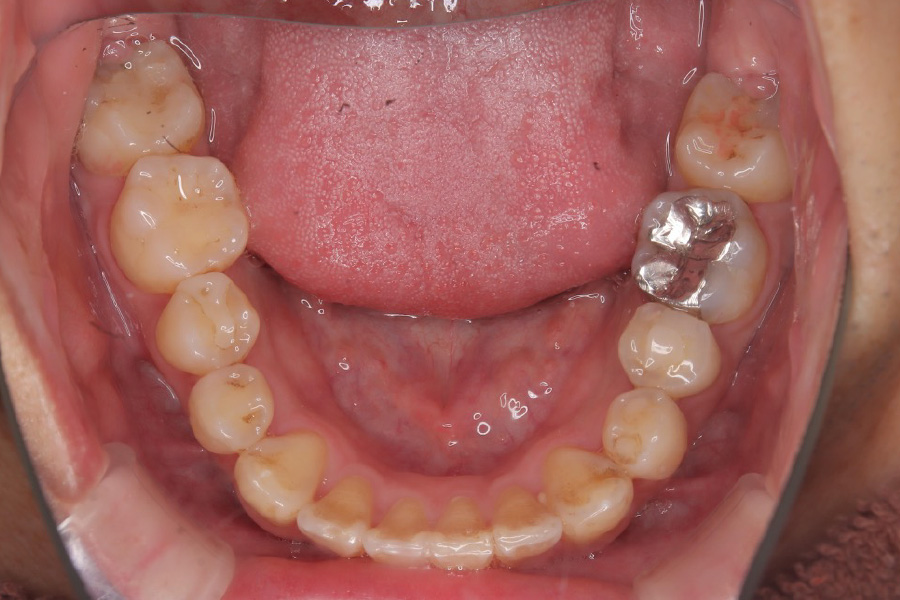

治療前

主訴 歯全体のガタつきが気になる

治療内容 インビザライン矯正

小臼歯抜歯